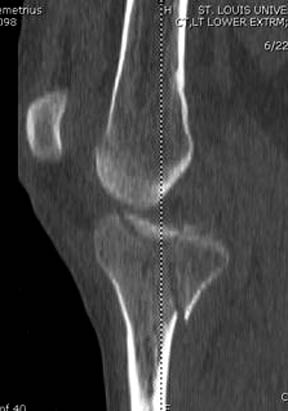

Вытяжение или наружный фиксатор “бедро-голень в виде дельты”. Фиксатор дает свободу, и если условия позволяют, можно отпускать домой. Но главное - надо ожидать проявления “wrinkle sign”! После дистракции можно делать КТ исследование, иначе нестабильные фрагменты искажают данные. Доступ делается по топографии расположения фрагментов, а 3Д картина лучше покажет расположение смещенных мыщелков.

Еще одно дополнение, некоторые в прочтении перелома медиального мыщелка делают типичные ошибки, например, редко переломы медиального мыщелка бывают “только медиальными”, а часто с наличием сложного, заднего компонента, который часто смещается кзади.

На боковом рентгене, явный задний смещенный компонент. КТ поможет увидеть "вершину" перелома, куда надо поставить антискользящую пластину из заднего или задне-медиальнего доступа. Для стабилизации боковой колонны традиционный боковой доступ через Girdle tubercle с длинной блокирующей пластиной. Одна задняя подпорка не удержит медиальную колонну, требуется длинная медиальная пластина.